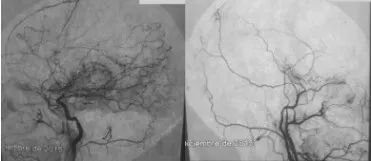

烟雾病是一种罕见的慢性、进行性脑血管疾病。它以颈内动脉末端及其主要分支的狭窄或闭塞为特征,并伴随着脑底部异常血管网的形成,这些异常血管在血管造影中呈现类似“烟雾”的模糊影像,因此得名。

血管造影显示烟雾病

患者出现中风、偏瘫、癫痫等症状。烟雾病是青年卒中的主要病因之一,但其发病机制尚未明确,可能与遗传、免疫、炎症等多种因素有关。